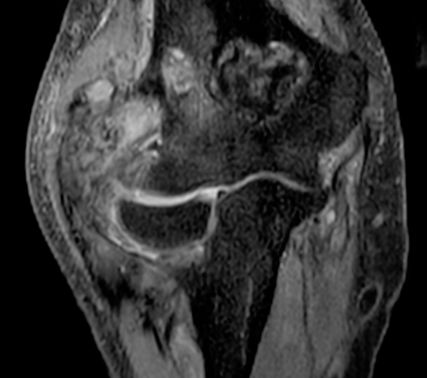

Das Nebenwirkungsprofil der Kombinationstherapie entsprach dem der publizierten Daten zur Monotherapie mit Sunitinib. Die Ergebnisse von Teil 2 der Peak-Studie, für den aktuell Patient:innen rekrutiert werden, mit Randomisierung für Bezuclastinib 600mg/Tag+Sunitinib vs. Sunitinib, bleiben abzuwarten, wobei die Ansprechrate bisher Erfolg versprechend ist (Abb.1).18